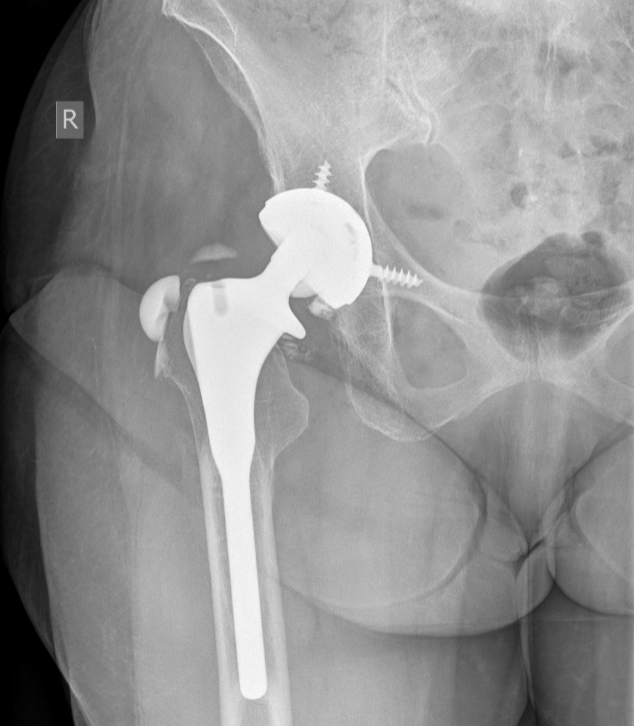

3. Shattered ceramic femoral head arthroplasty